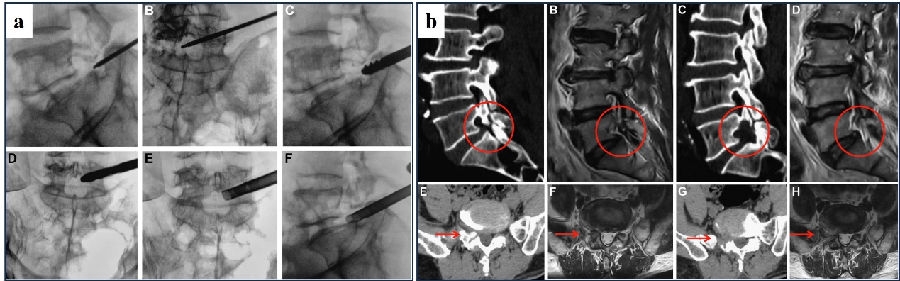

Chen Bin等人[19]使用椎间孔镜技术治疗L5/S1峡部裂性滑脱所致的椎间孔狭窄,95%的患者在1年的随访时间里获得满意的治疗效果(图16)。他们认为成人峡部裂性滑脱往往是自发稳定而很少进展,对于稳定的峡部裂性滑脱所致的神经压迫,椎间孔镜技术是一种简单有效、性价比高及创伤更小的手术,且不会影响脊柱稳定性。但仍然需要有更长期的随访结果来验证其远期疗效以及是否对脊柱稳定性产生影响。

图16:a.术中工作通道透视位置;b.典型病例术前术后影像学对比。